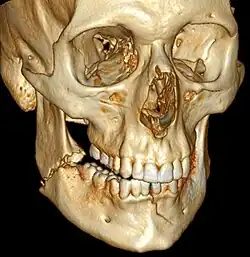

![]() | |

| 3D computed tomographic image of a mandible fracture in two places. One is a displaced right angle fracture and the other is a left parasymphyseal fracture. | |

Computed tomography is the most sensitive and specific of the imaging techniques. The facial bones can be visualized as slices through the skeletal in either the axial, coronal or sagittal planes. Images can be reconstructed into a 3-dimensional view, to give a better sense of the displacement of various fragments. 3D reconstruction, however, can mask smaller fractures owing to volume averaging, scatter artifact and surrounding structures simply blocking the view of underlying areas.